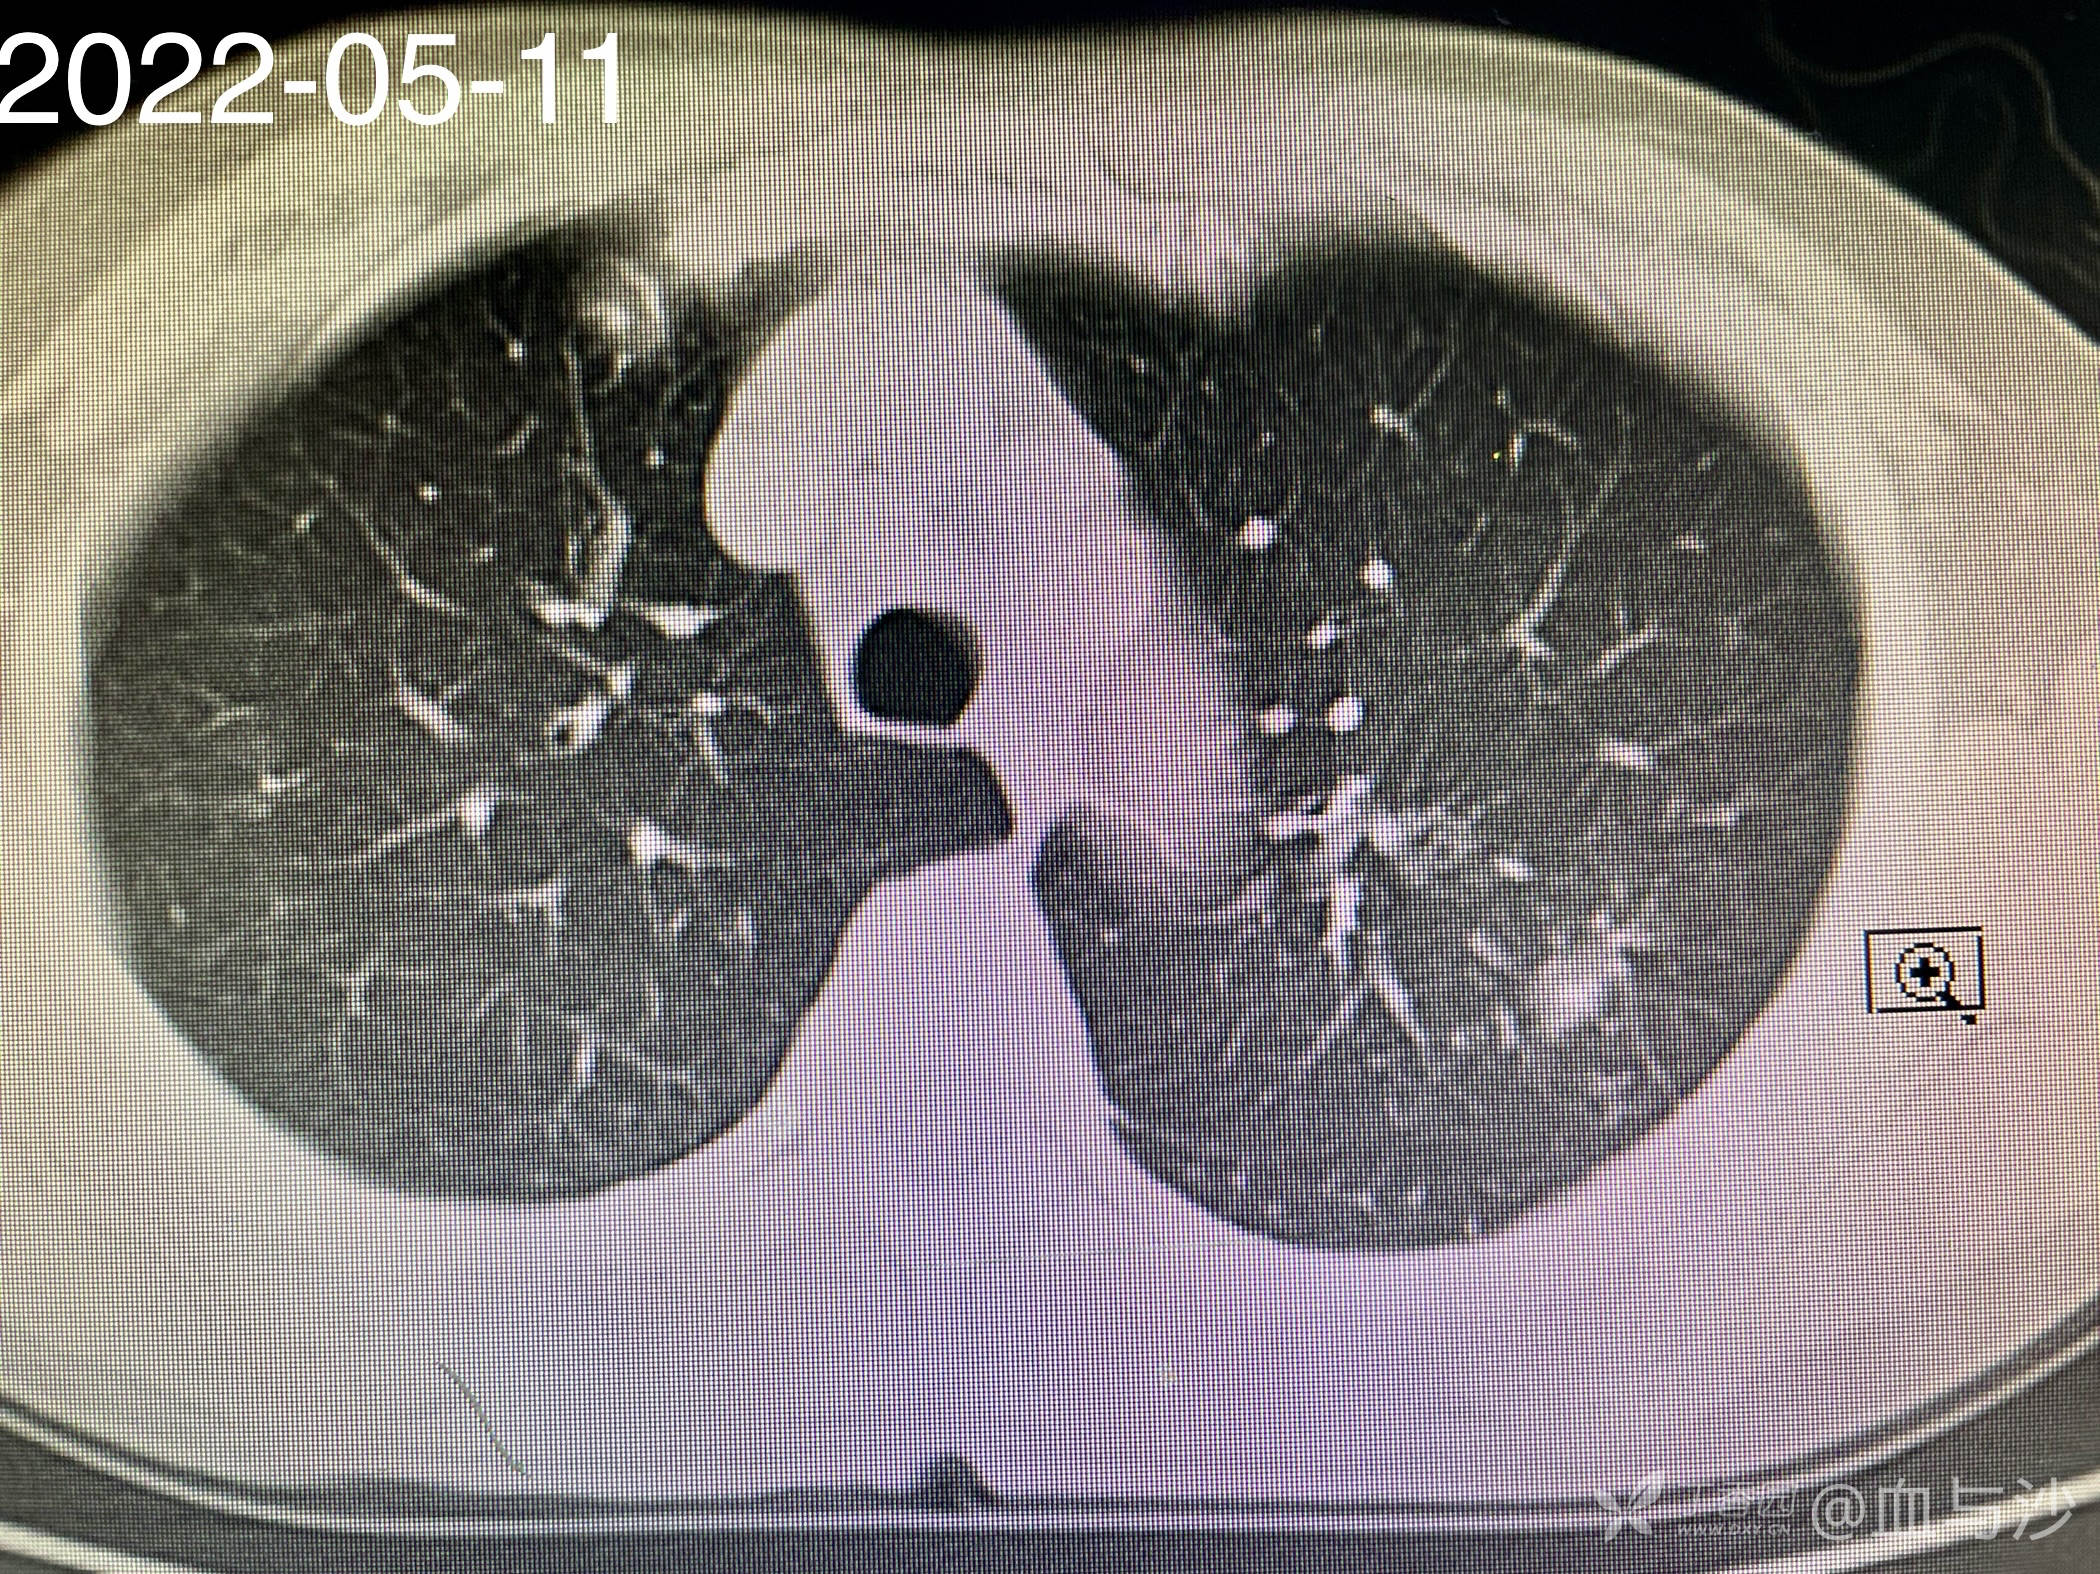

以下是今年5月的CT影像:

病人女,60岁,去年4月底因咳嗽发热入院,诊断支气管扩张伴感染(结核各项检查阴性,病人平时也无潮热盗汗),予抗感染对症处理。当时CT片左肺上叶有一磨玻璃样影。今年5月病人再次咳嗽发热入院,续按照支扩伴感染处理,但CT显示去年的磨玻璃影成了一约1.5cm的实性结节。

大伙帮看看呢,除了肿瘤还有没有其他可能🤔